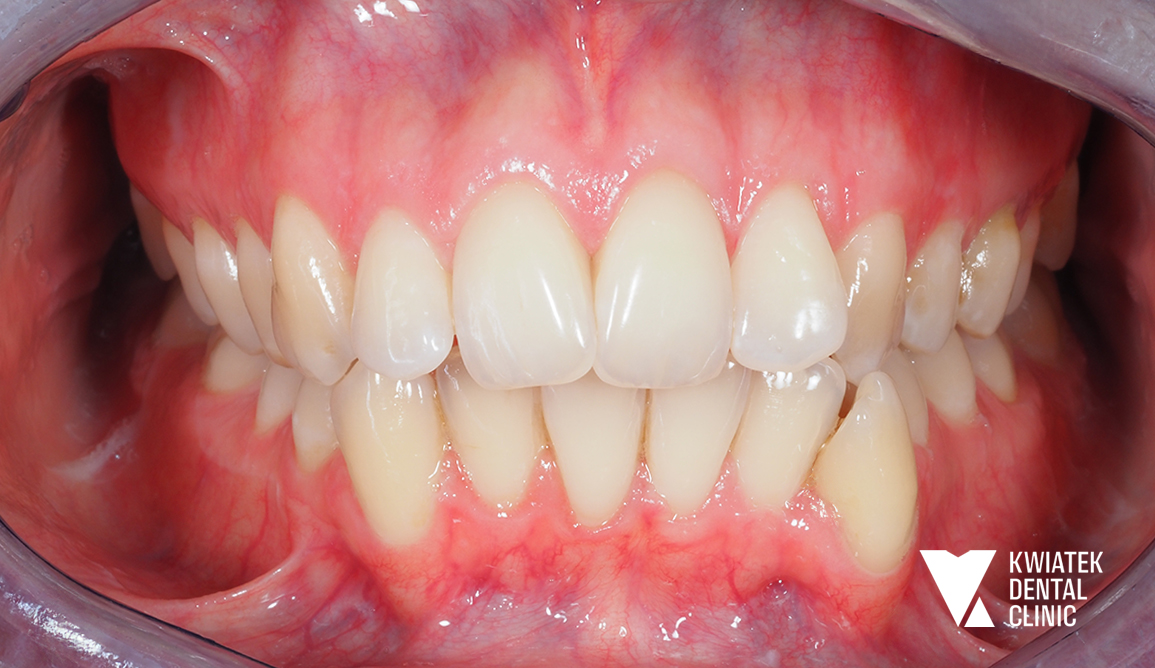

Luksus dyskretnej ortodoncji oparty na zaawansowanej technologii nakładkowej

Pacjentka zgłosiła się do kliniki z potrzebą kompleksowej poprawy zarówno funkcji zgryzu, jak i estetyki uśmiechu. W badaniu stwierdzono zgryz krzyżowy, stłoczenia zębów oraz liczne problemy wymagające leczenia zachowawczego i protetycznego, co wymagało wieloetapowego, interdyscyplinarnego podejścia. Terapię poprzedziło staranne przygotowanie jamy ustnej obejmujące ekstrakcję zębów mądrości, profesjonalną higienizację oraz odbudowę osłabionych struktur. Następnie wdrożono zaawansowane leczenie ortodontyczne z wykorzystaniem nowoczesnego systemu nakładkowego. Rezultatem jest harmonijny, stabilny zgryz, idealnie ukształtowane łuki zębowe oraz wyraźnie odmłodzony, jasny uśmiech, podkreślony profesjonalnym wybielaniem.